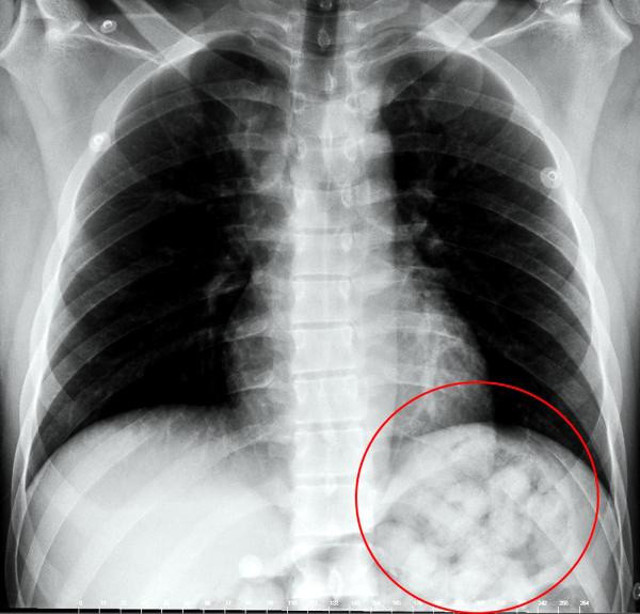

Abone olVan'dan otobüs ile Ankara'ya gelen İran uyruklu Zadeh Ahmed Narziveh, Ankara Şehirlerarası Terminal İşletmesi'nde fenalaştı. Zarziveh, çevredekilerin haber vermesiyle gelen 112 Acil Servis ekiplerinin ilk müdahalesinin ardından Ankara Şehir Hastanesi'ne kaldırıldı. Tedavi altına alınan Narziveh'in çekilen röntgen filminde midesinde cisim tespit edildi.

Ameliyata alınan Zarziveh'in midesinden 2'si patlamış 72 adet kapsül halinde uyuşturucu madde çıkarıldı. Gördükleri manzara halinde şaşkına dönen doktorlar durumu polise bildirdi. Gelen polis ekiplerinin yaptığı incelemede 890 gram uyuşturucu maddenin metamfetamin olduğu belirlendi.